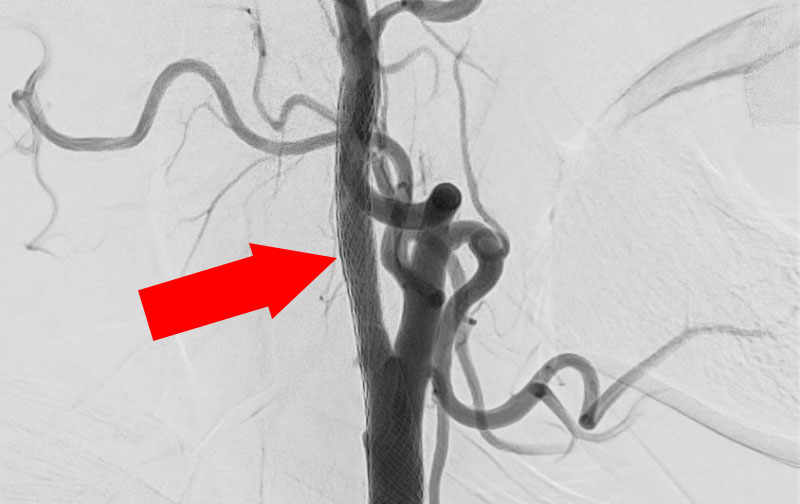

1188

'22年2月14日

右頚部内頚動脈狭窄症

70代

大阪府の病院

手術写真

治療

前

中

後

手術日